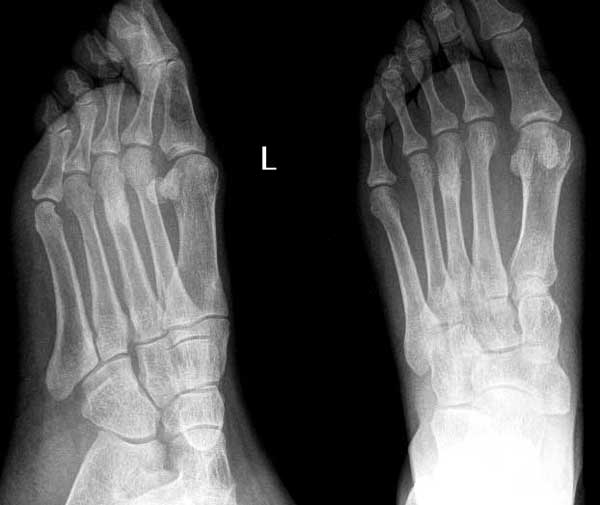

以下是引用常山真人在2004-7-20 9:50:49的发言:[br]第3遮骨疲劳性骨折[br]左足第1趾-似---囊性病变(片不太清晰) 1-正常 2-如是囊性病变多为内生性软骨瘤。[br][br][本贴已被 常山真人 于 2004-7-20 9:53:09 修改过]

以下是引用rjbjl在2004-7-20 21:39:14的发言:[br]应该是第三蹠骨疲劳型骨折[br]zhi骨

以下是引用www123456在2004-7-20 23:17:45的发言:[br]典型的第三跖骨 疲劳骨折。[br]对于第一趾骨的病变怀疑是没有根据的,斜位所见影像是由于第一趾的跖趾关节软组织和骨皮质凑成的。在正位片可见第一趾的骨质是完好的。